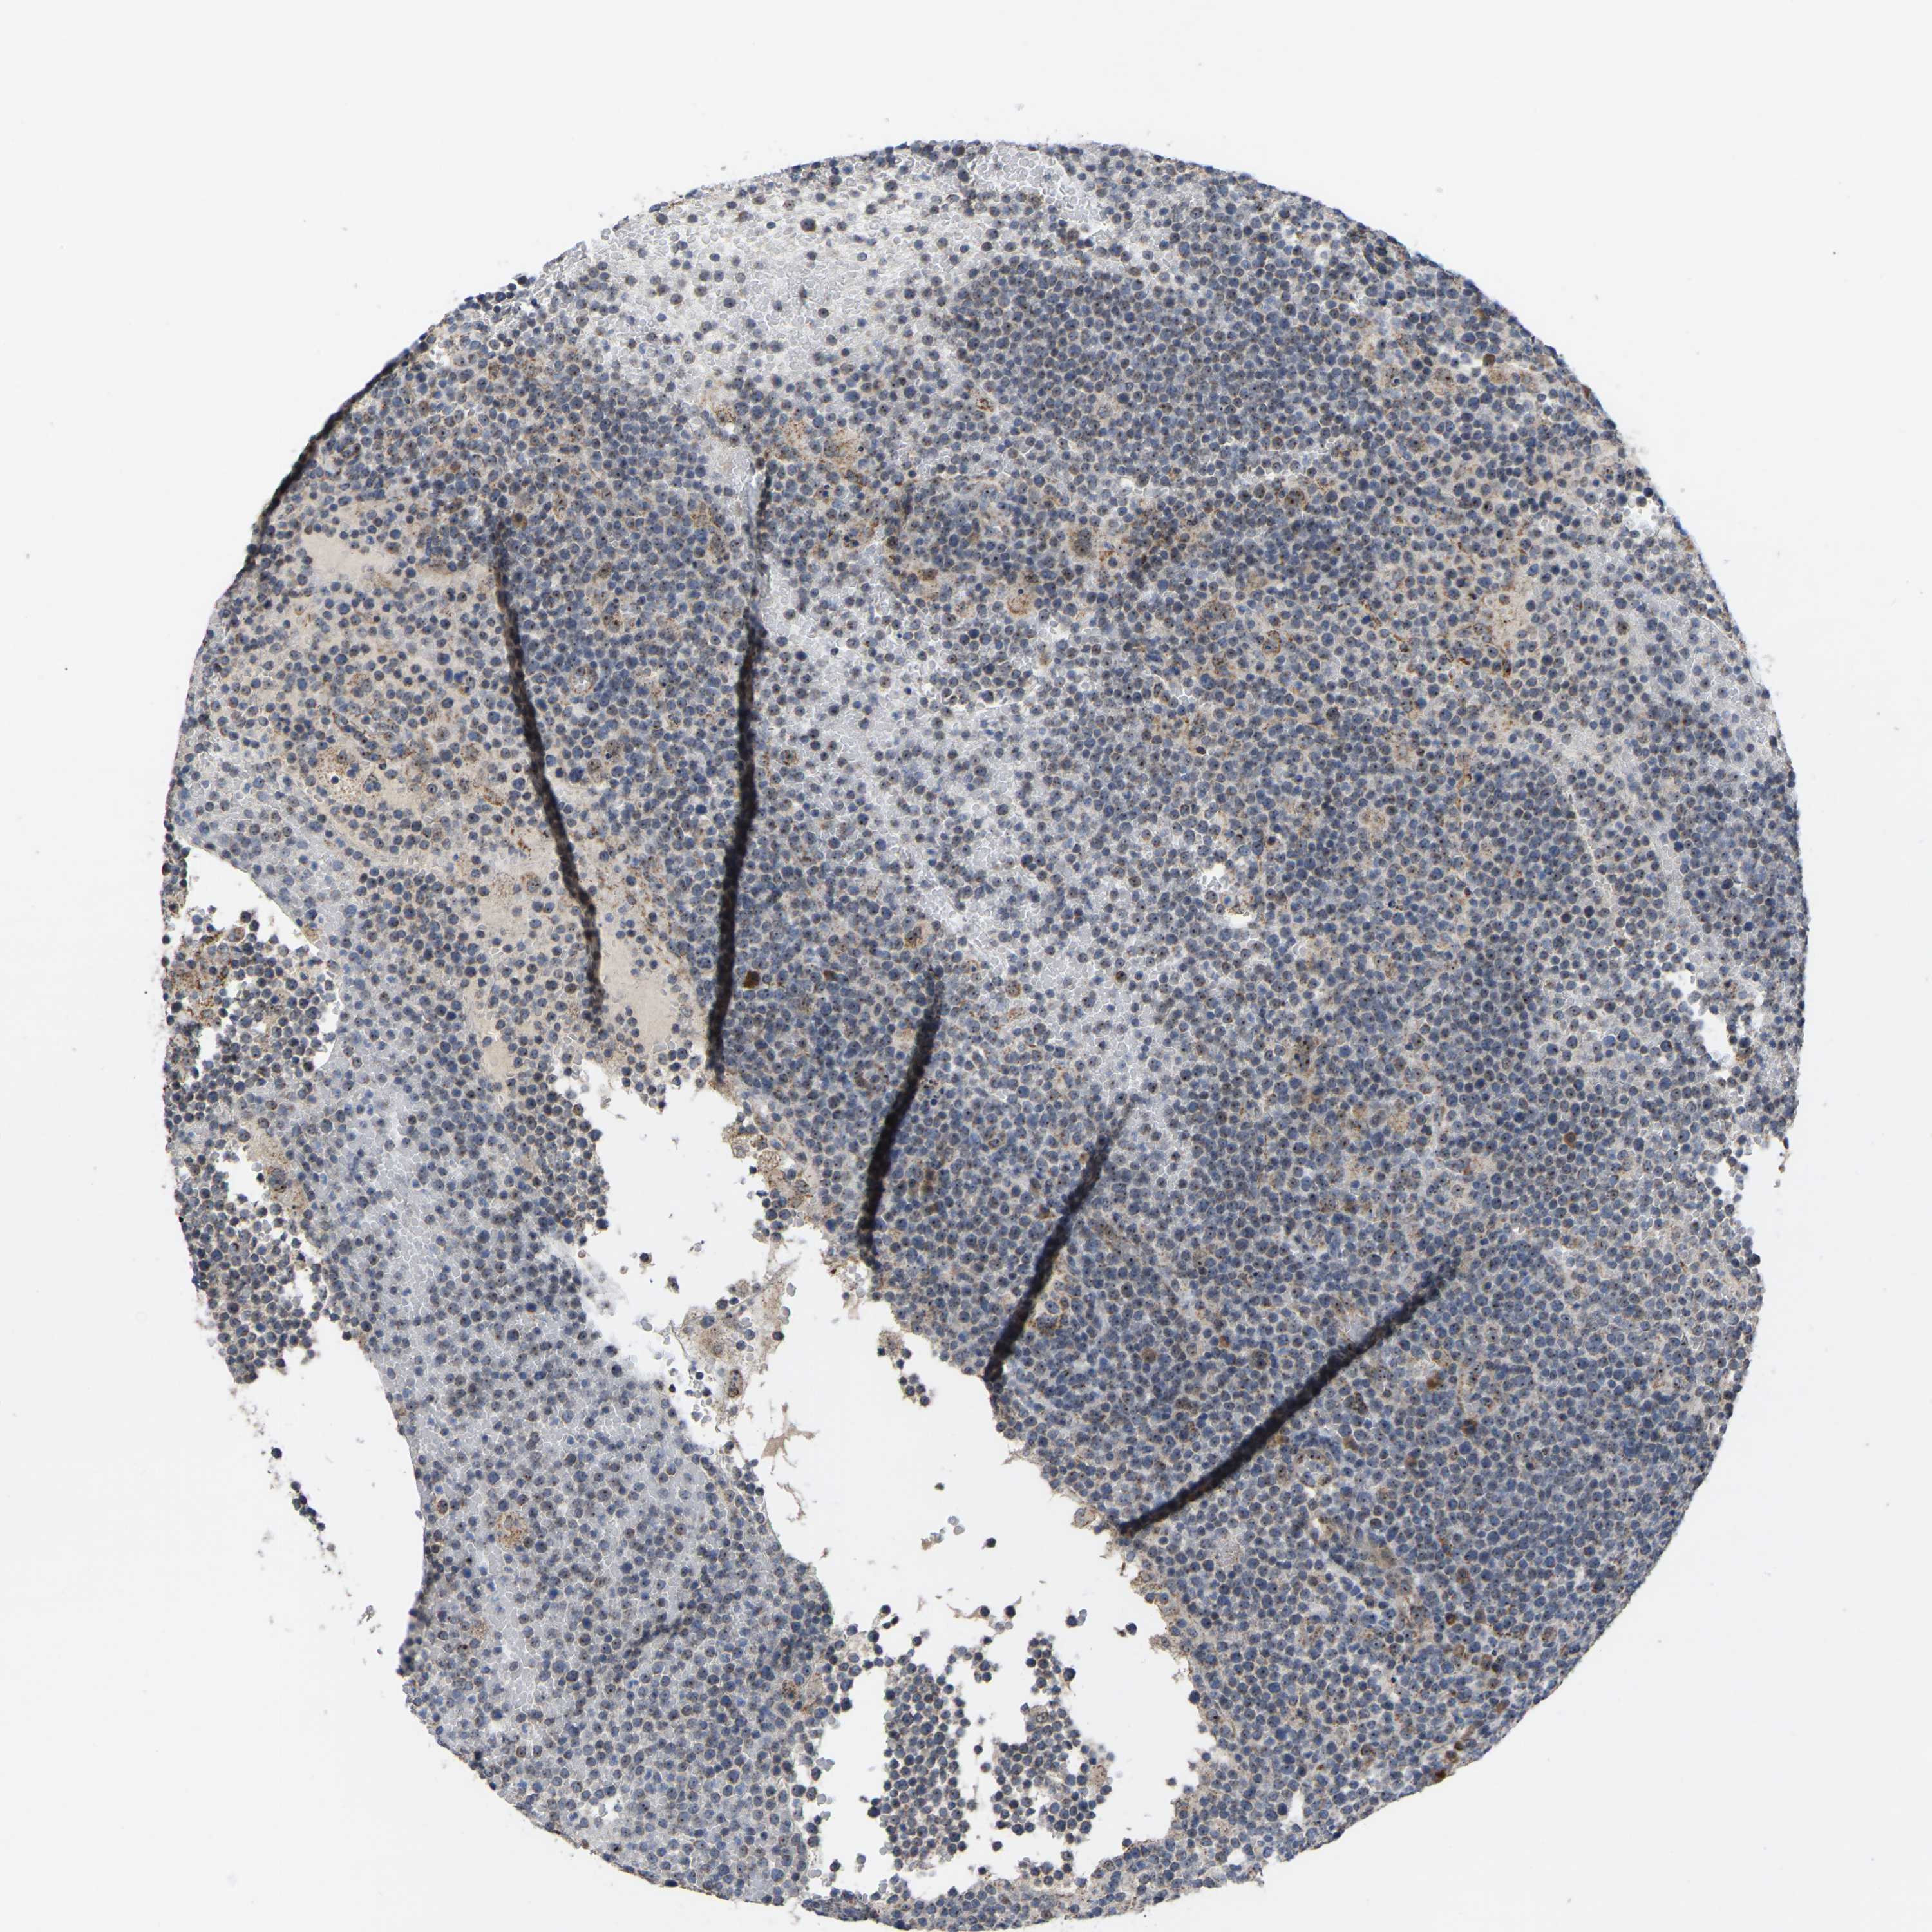

CANCER LYMPHOMA Show tissue menu

LYMPHOMA - Protein expressioni

A mouse-over function shows sample information and annotation data. Click on an image to view it in a full screen mode. Samples can be filtered based on level of antibody staining by selecting one or several of the following categories: high, medium, low and not detected. The assay and annotation is described here.

Each image is clickable and will lead to virtual microscopy that enables deeper exploration of all samples and also displays staining intensity scores, fraction scores and subcellular localization as well as patient and tissue information for each sample.

Antibody HPA018999

Hodgkin's disease, NOS

Malignant lymphoma, non-Hodgkin's type, High grade

Malignant lymphoma, non-Hodgkin's type, Low grade